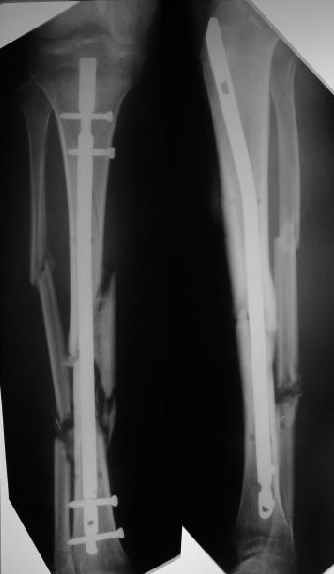

Наконец, 23 марта сделали и голень.

Сергей Зырянов 10 Апрель 2004, 19:43

Пациент вернулся. Результаты лечения удовлетворяют его.

Буду продолжать наблюдать, лечить.

Раны зажили хорошо, швы снял. Сделали контрольный рентгеновский снимок бедра. Движения в коленном суставе востанавливаются, угол 94 гр.

Больной ходит пока с костылями, с неполной нагрузкой весом тела, он боится больше нагружать.